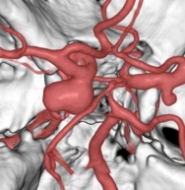

未破裂脳動脈瘤とは

脳の中の比較的太い血管に出来た瘤(コブ)で、ほとんどの場合、無症状ですが、破裂すると出血して、クモ膜下出血になります。クモ膜下出血は脳卒中(脳血管障害)の中でも最も予後が悪い病気と言われており、発症すると、死亡例が約1/3、後遺症の残る例が約1/3、元気に回復する方は約1/3と言われています。